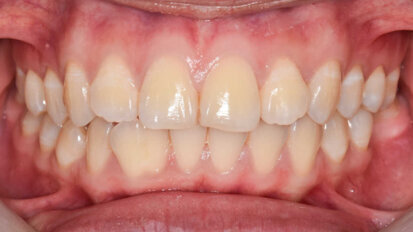

Digitální vs. analogový pracovní postup u keramických fazet v horní čelisti

Pro frontální úsek chrupu je v estetické a záchovné stomatologii k dispozici mnoho různých materiálů a možností léčby. Konvenční protokol, ...